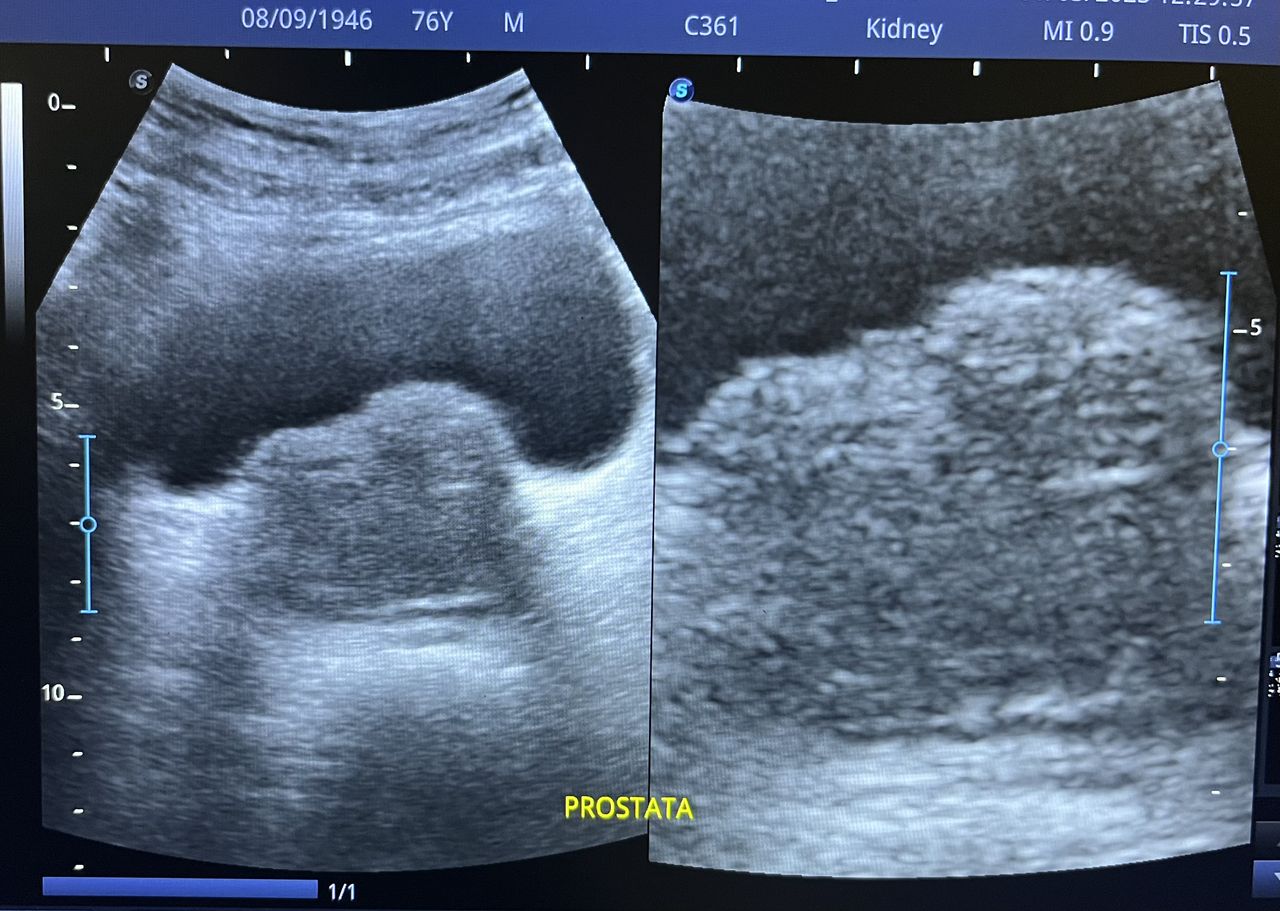

Médico general con 15 años de experiencia, master en enfermedades infecciosas y antibioticoterapia por parte de la Universidad Cardenal Herrera en Valencia, ademas de diversos diplomados en el área de Infectología y Parasitología, Urgencias, Imagenología y Medicina del Trabajo. He laborado en Hospitales y Clínicas en el área de Urgencias, en Laboratorios realizando estudios de Imagen, en especifico ultrasonidos de todo tipo desde básicos hasta avanzados incluidos los obstétricos estructurales, en Secretaría de Salud del Estado de Querétaro realizando ultrasonidos obstétricos para la detección de malformaciones en los tres trimestres del embarazo en diversos centros de salud, como médico de Empresas en el campo de Salud Laboral y actualmente en este consultorio en donde para su mejor atención y siempre buscando integrar la mayoría de las herramientas diagnosticas cuento con equipo de ultrasonido como apoyo en la exploración del paciente o como servicio diagnostico por imagen, realizo ultrasonidos convencionales (hepatobiliar (hígado, páncreas, vesícula y bazo), vías urinarias, ginecológico abdominal y transvaginal, tiroideo, prostático, testicular, pared abdominal) y especializados (dopler obstétrico en los 3 trimestres de embarazo), musculoesquelético en lesiones deportivas. También cuento con un equipo de electrocardiograma de 12 derivaciones para monitoreo completo del funcionamiento cardiaco, espirometria para evaluar la función pulmonar en la consulta, pruebas rápidas que se realizan en consultorio para detectar de forma mas precisa enfermedades infecciosas como Influenza A y B, covid19, infecciones urinarias, dengue, zika, chikungunya. Cuento con diversas vacunas para prevención de enfermedades. Siempre con el objetivo de dar el mejor servicio y atención a su salud. Lo espero en consulta para escucharlo y estudiar su caso de la forma más completa posible, estoy seguro de que tendremos las mejores opciones para su tratamiento. Mi tranquilidad es que usted se vaya con todas sus preguntas e inquietudes resueltas.

• Ultrasonio de riñones

$800